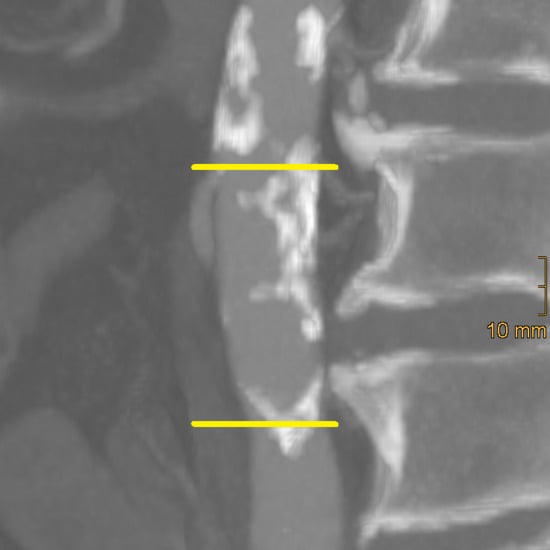

2.2. Assessment of Vascular Calcification

2.2.1. Abdominal Aortic Calcification